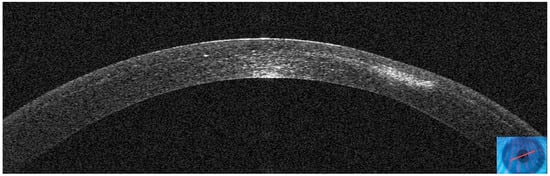

3.2. Patient #2